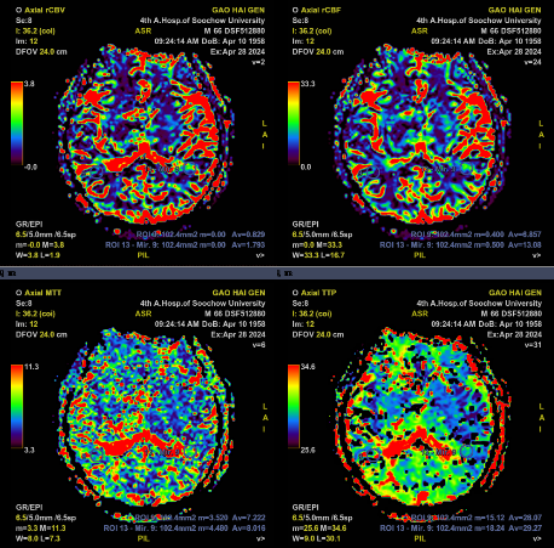

术前PWI:右侧岛叶、颞叶、右侧脑室旁及放射冠区CBF、CBV减低,MTT、TTP较对侧延长

术后PWI:右侧岛叶、颞叶、右侧脑室旁及放射冠区血流明显改善